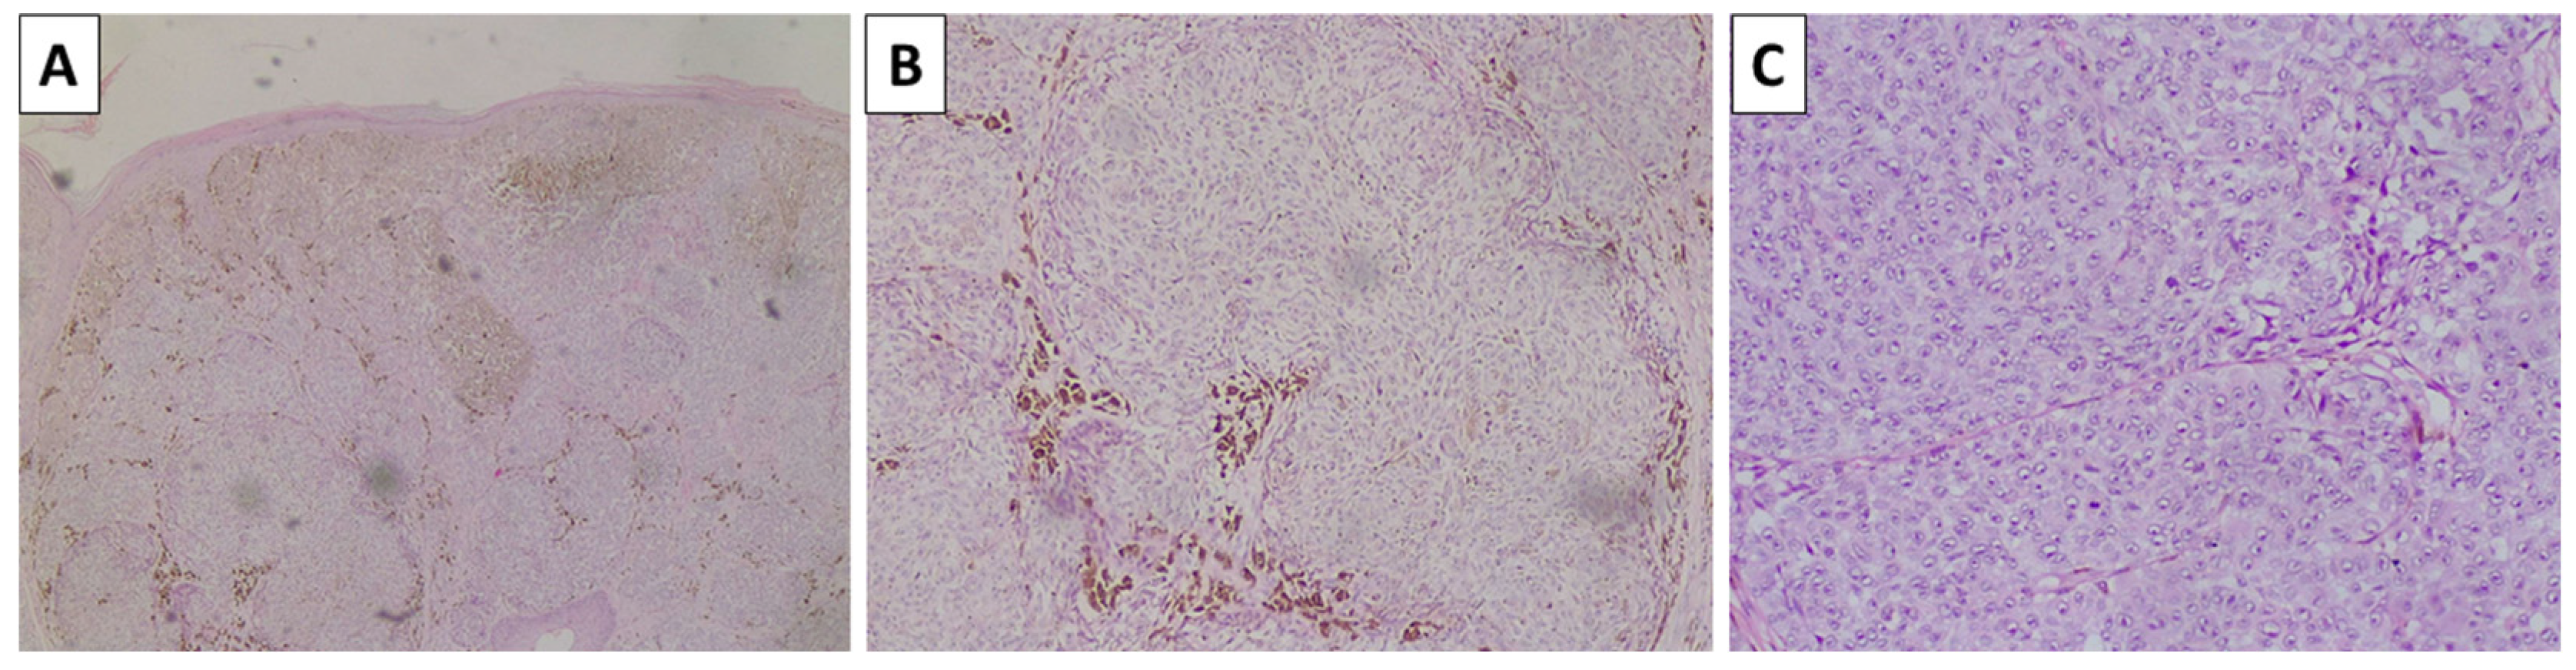

The lesion on the cheek, histologically, was represented by an atrophic epidermis and a melanocyte lesion with well-defined borders involving the epidermis and extending to the reticular dermis, composed of areas of marked pigmentation and cellularity, with oval to spindle-shaped cells with small monomorphic nuclei, speckled chromatin, and more abundant light or finely pigmented cytoplasm. The tumor cells are arranged in short fascicles and nests, surrounded by pigmented macrophages and circumscriptive sclerotic stroma. Hence, the lesion was diagnosed as a cellular blue nevus (Figure 4). The second lesion histologically was represented by an acanthotic lesion comprising large squamoid cells with light cytoplasm and easily identifiable mitoses, forming intraepidermal nests with microabscesses, single concentric keratin deposits, and focal ulceration. Hence, the lesion was diagnosed as a squamous cell carcinoma in situ (Figure 5). No basement membrane penetration was noted with a dense lichenoid infiltrate located under the lesion. The third lesion was histologically represented by a pigmented lesion with an asymmetric profile, comprising a dermally located neoplastic proliferation of epithelioid-type cells that progressed beyond the border of the dermal component, with nesting structures at the dermoepidermal junction and pagetoid spread. The tumor cells exhibited marked pleomorphism and eosinophilic cytoplasm, as well as vesicular nuclei and prominent nucleoli. An abundance of pigmented macrophages accompanied the sparse intervening stroma, and the pigmentation varied from apigmented to coarsely pigmented. No marked lymphocytic infiltrate, necrosis, or erosion of the surface epithelium was noted. However, the lesion extended to the reticular dermis (Clark IV) and had an overall thickness of 3 mm (Breslow stage III), without epidermal ulceration, the presence of vascular emboli, or atypical mitoses less than 5 per square millimeter (Figure 6). The neighboring pigmented lesion was represented by an epidermally based nevomelanocytic lesion comprising poorly pigmented cells and nests in the dermis, featuring nonpigmented nevomelanocytes with focal low-grade cytological atypia. Hence, the lesion was diagnosed as pT3a melanoma. The patient was referred to the oncology committee for treatment and is currently undergoing treatment and monitoring with stable disease and no progression of either the melanocytic or squamous cell neoplasia.

Figure 6.

Histopathology of the scalp lesion. (A) pigmented lesion with superficial dermal involvement, original magnification 40×; (B) large nest of neoplastic melanocytes with subtle pigmentation, original magnification 100×; (C) atypical melanocytes with increased mitotic activity, original magnification 200×; stains (A–C) hematoxylin and eosin.